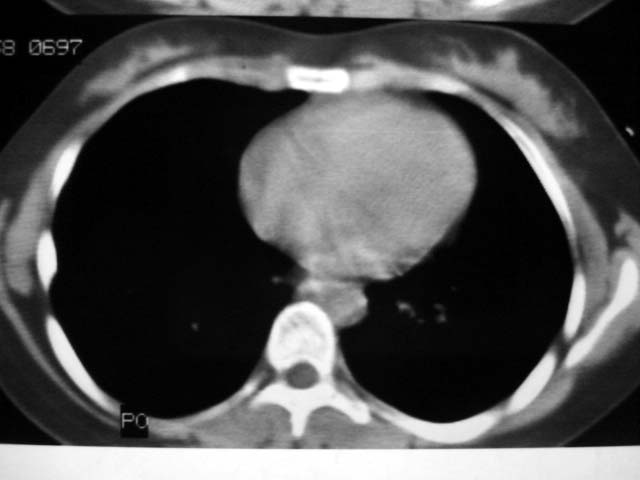

标题: CT12463:女,19岁,炎性假瘤?结核球? [打印本页]

标题: CT12463:女,19岁,炎性假瘤?结核球?

女,19岁,体检时发现。炎性假瘤?结核球?

纵隔窗肿块明显较肺窗小,切粗长毛刺,“倒核桃”征:考虑炎性假瘤

考虑炎症,抗炎后复查。理由:病变肺窗显示的大小明显大于纵隔窗,提示病变周围为密度偏低的渗出改变。不同于结核球和肿瘤。